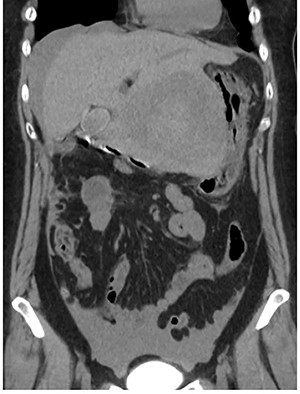

A 56-year-old woman presented to another hospital with acute abdomen. Computed tomography (CT) examination demonstrated a tumor 10 cm in diameter that protruded from the left lateral segment of the liver, with evidence suggestive of rupture of the liver tumor (Fig. 1). Since the patient was in good general condition, she was referred to our hospital for further evaluation. Her blood biochemical parameters when she was referred to our hospital were hemoglobin: 11.6 g/dl, albumin: 3.4 g/dl, γ-globulin: 18.5% and anti-acetylcholine receptor antibody: <0.3 nmol/L. Dynamic CT presented a liver tumor 10 cm in diameter, which was located at the left lateral segment of the liver, with a clear margin. A mass with an irregular margin was also identified in the anterior mediastinum (Fig. 2). On percutaneous angiography, since obvious extravasation of the contrast medium could not be identified, the arteries of the left lateral segment were embolized to prevent re-bleeding. Although a definitive preoperative diagnosis could not be made using magnetic resonance imaging (MRI) (Fig. 3), fluorodeoxyglucose positron emission tomography (FDG) showed increased FDG uptake in both the hepatic and anterior mediastinal tumors (Fig. 4). Although the liver tumor was suspected to be metastasis secondary to a thymoma based on the clinical findings, percutaneous tumor biopsy was performed to confirm the pathological diagnosis. The biopsy suggested malignant T-cell lymphoma or metastatic thymoma. In order to prevent re-rupture of the hepatic tumor, to confirm the pathological diagnosis and to potentially achieve a curative resection, the patient underwent laparoscopic left lateral segmentectomy (Fig. 5). Although the tumor was found to be adherent to the stomach, blunt dissection was possible. In addition, no peritoneal dissemination was detected. The surgical duration was 212 min and estimated blood loss was 50 ml. The liver tumor was pathologically diagnosed as metastatic thymoma type AB (Fig. 6). The patient’s postoperative course was uneventful and she subsequently underwent radical thymectomy 3 months after the liver resection. The thymic tumor was pathologically diagnosed as thymoma type B2. Currently, 30 months after thymectomy, she remains free from tumor recurrence.

Contrast-enhanced CT. (a) Abdominal CT: a solitary liver tumor, 10 cm in diameter, was located in the left lateral segment of the liver. The tumor had a clear margin, with tumor enhancement in both the arterial and portal phases. (b) Chest CT: an enhanced tumor with an irregular margin was detected in the anterior mediastinum. The tumor had a maximum diameter of 4.5 cm.